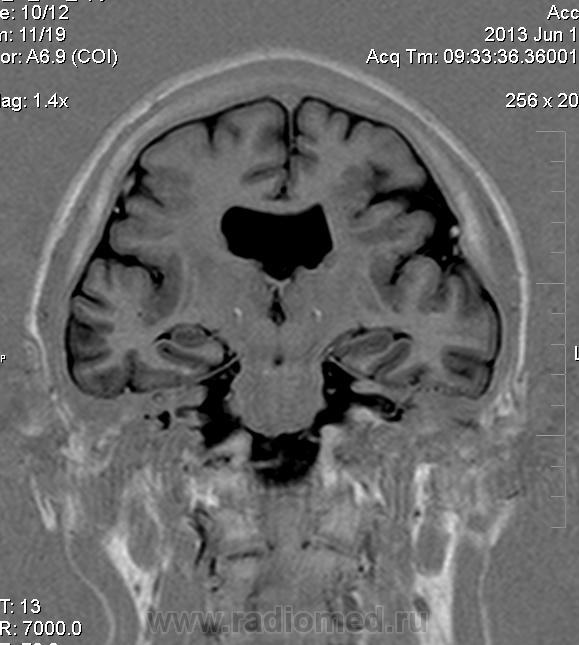

Мужчина 32 лет. Из анамнеза: перинатальное повреждение ЦНС, ДЦП, дизартрия, правосторонний верхний монопарез. С 16 лет приступы эпилепсии.

Аплазия прозрачной перегородки. Шизэнцефалия с открытыми краями в лобно-теменной области слева. Шизэнцефалия с закрытыми краями в лобной области справа? Утолщение коры по контуру расщелин и в области глазничной извилины правой лобной доли. Микрогирия? Гиперостоз костей свода черепа. Уважаемые коллеги, возможно я ошибаюсь, или есть еще аномалия?

сочетания отсутствия прозрачной перегородки и дисплазии ( разно степени выраженности) зрительных неровов  указывает на септоптическую дисплазию-нарушение развития в области средней линии , сопровождается мнггими другими структурными аномалиями, чаще шизэнцефалией.

На мой взгляд, полимикрогирия двусторонняя (конвекситальные отделы дорзальных отделов лобных долей и частично теменных, а также в базальном отделе полюса правой лобной доли) + закрытая шизенцефалия левой лобно-теменной области. Аплазия прозрачной перегородки (как признаки лобарной голопрозенцефалии).